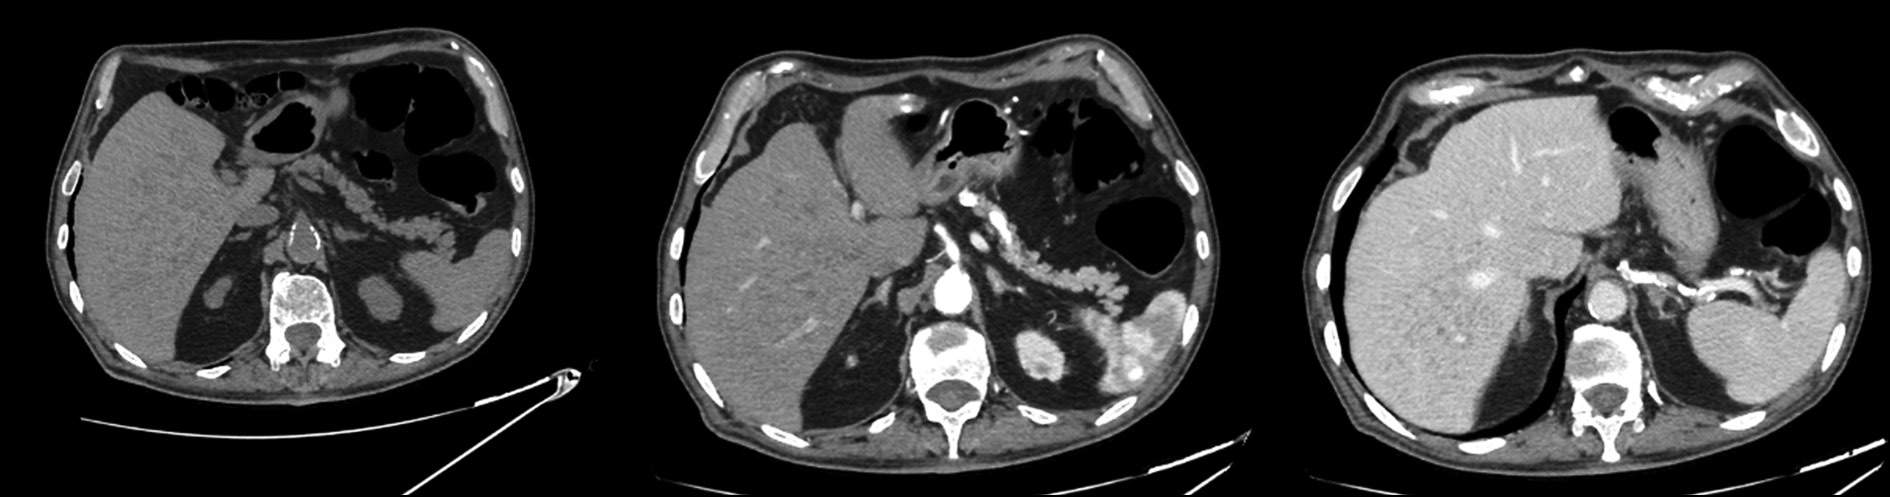

Role of artificial intelligence and novel visualization techniques in the early diagnosis of pancreatic cancer: a review

Abstract

Pancreatic ductal adenocarcinoma is the most common pancreatic cancer. It is characterized by a progressive course or distant metastases in 80%–85% of cases. Despite advances in understanding of pancreatic ductal adenocarcinoma, the disease is consistently linked to poor prognosis due to late diagnosis and limited treatment options in advanced stages. Recently, image processing using artificial intelligence has been introduced for pancreatic ductal adenocarcinoma diagnosis and demonstrated promising results. This review summarizes current scientific data, evaluates the role of artificial intelligence in imaging and early detection of pancreatic ductal adenocarcinoma, and identifies issues that warrant further investigation. The search for publications was conducted using PubMed, Google Scholar, and eLibrary. The following Russian and English search keywords were used: ранняя диагностика рака поджелудочной железы (early diagnosis of pancreatic cancer), искусственный интеллект (artificial intelligence), протоковая аденокарцинома поджелудочной железы (pancreatic ductal adenocarcinoma), медицинская визуализация (medical visualization), наночастицы (nanoparticles), pancreatic cancer, artificial intelligence, early diagnosis pancreatic ductal adenocarcinoma, and pancreatic cancer imaging. Significant progress in early detection of pancreatic ductal adenocarcinoma using artificial intelligence technologies was observed. Current approaches include pre-imaging risk stratification and increased data volume by analyzing electronic medical records. Despite substantial achievements, the clinical implementation of artificial intelligence technologies remains challenging. The use of artificial intelligence along with biomarkers is a promising direction and may enhance theranostics of various malignancies, including pancreatic ductal adenocarcinoma.

317-330